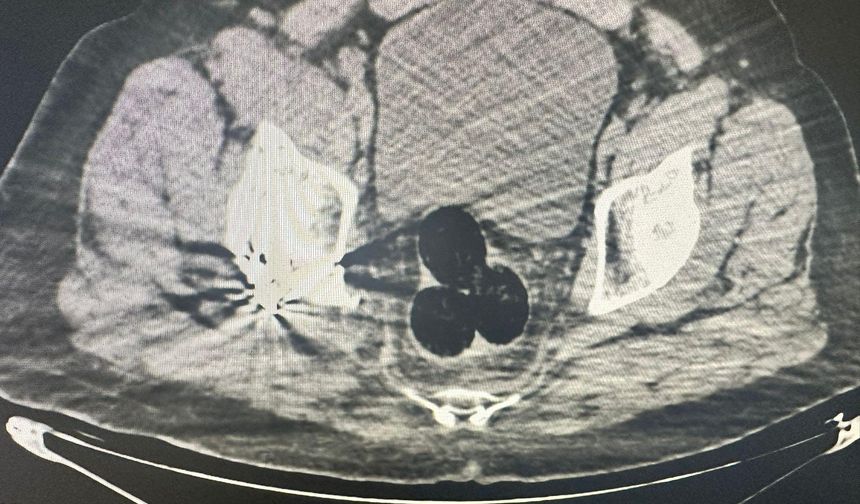

Radyolojik muayenede vücudunda 140 gram uyuşturucu çıkan şüpheli tutuklandı

Uyuşturucuyu makatına saklamış